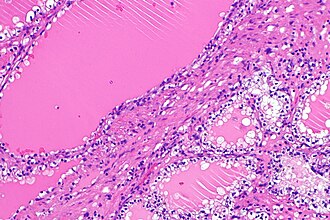

Renal cell carcinoma with clear cells and leiomyomatous bands. H&E stain. | |

| LM | leiomyomatous capsule of variable thickness, tubular structures with (1) apical snouts, and (2) clear cells with basal nuclei and mild nuclear atypia |

- Leiomyomatous capsule of variable thickness - key feature.

- Tubular structures with:

- Apical snouts.

- Clear cells with basal nuclei and mild nuclear atypia.